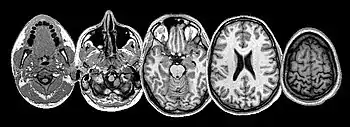

Many brain structures and physiological processes are involved in suffering (particularly the anterior insula and cingulate cortex, both implicated in nociceptive and empathic pain).[27] Various hypotheses try to account for the experience of suffering. One of these, the pain overlap theory[28] takes note, thanks to neuroimaging studies, that the cingulate cortex fires up when the brain feels suffering from experimentally induced social distress, as well as physical pain. The theory proposes therefore that physical pain and social pain (i.e. two radically differing kinds of suffering) share a common phenomenological and neurological basis.